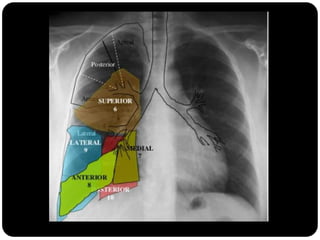

Traquéia       Pulmão direito:

Brônquios           LSD: anterior, apical e posterior;

Bronquíolos

      LM: medial e lateral;

Alvéolos

      LID: superior, basal medial, basal lateral,

basal anterior, basal posterior;

 Pulmão esquerdo:

     LSE: apicoposterior, anterior,

superior(língula), inferior(língula);

     LIE: segmento superior, basal antero-

medial, basal lateral e basal posterior;